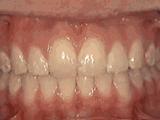

是不是很直观?看了这些图想要矫正的朋友是不是就安心了?